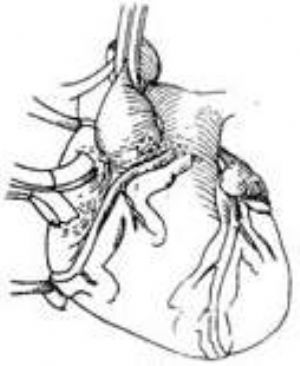

右冠狀動脈異位起源於肺動脈 右冠狀動脈異位起源於肺動脈較之左冠狀動脈遠爲少見,到1979年僅報道17例(LeBerg等),大多數病例不呈現臨牀症狀,在屍體解剖時才明確診斷。由於右心室壁薄,張力低,兩側冠狀動脈之間又可形成側支循環,因此右冠狀動脈分佈區域的心肌氧供仍能維持,嬰兒期不呈現臨牀症狀,生長發育亦無異常,進入成年期後,少數病人可出現心力衰竭或猝死。升主動脈和肺動脈造影檢查,可顯示異位起源的右冠狀動脈,從而明確診斷。

治療方法是在體外循環下施行手術,將右冠狀動脈開口連同其周圍的部分肺動脈壁從肺動脈切下後移位植入升主動脈根部前壁。由於右冠狀動脈較長,且起源於肺動脈前壁靠近升主動脈,移植術操作比較簡易(圖4)。